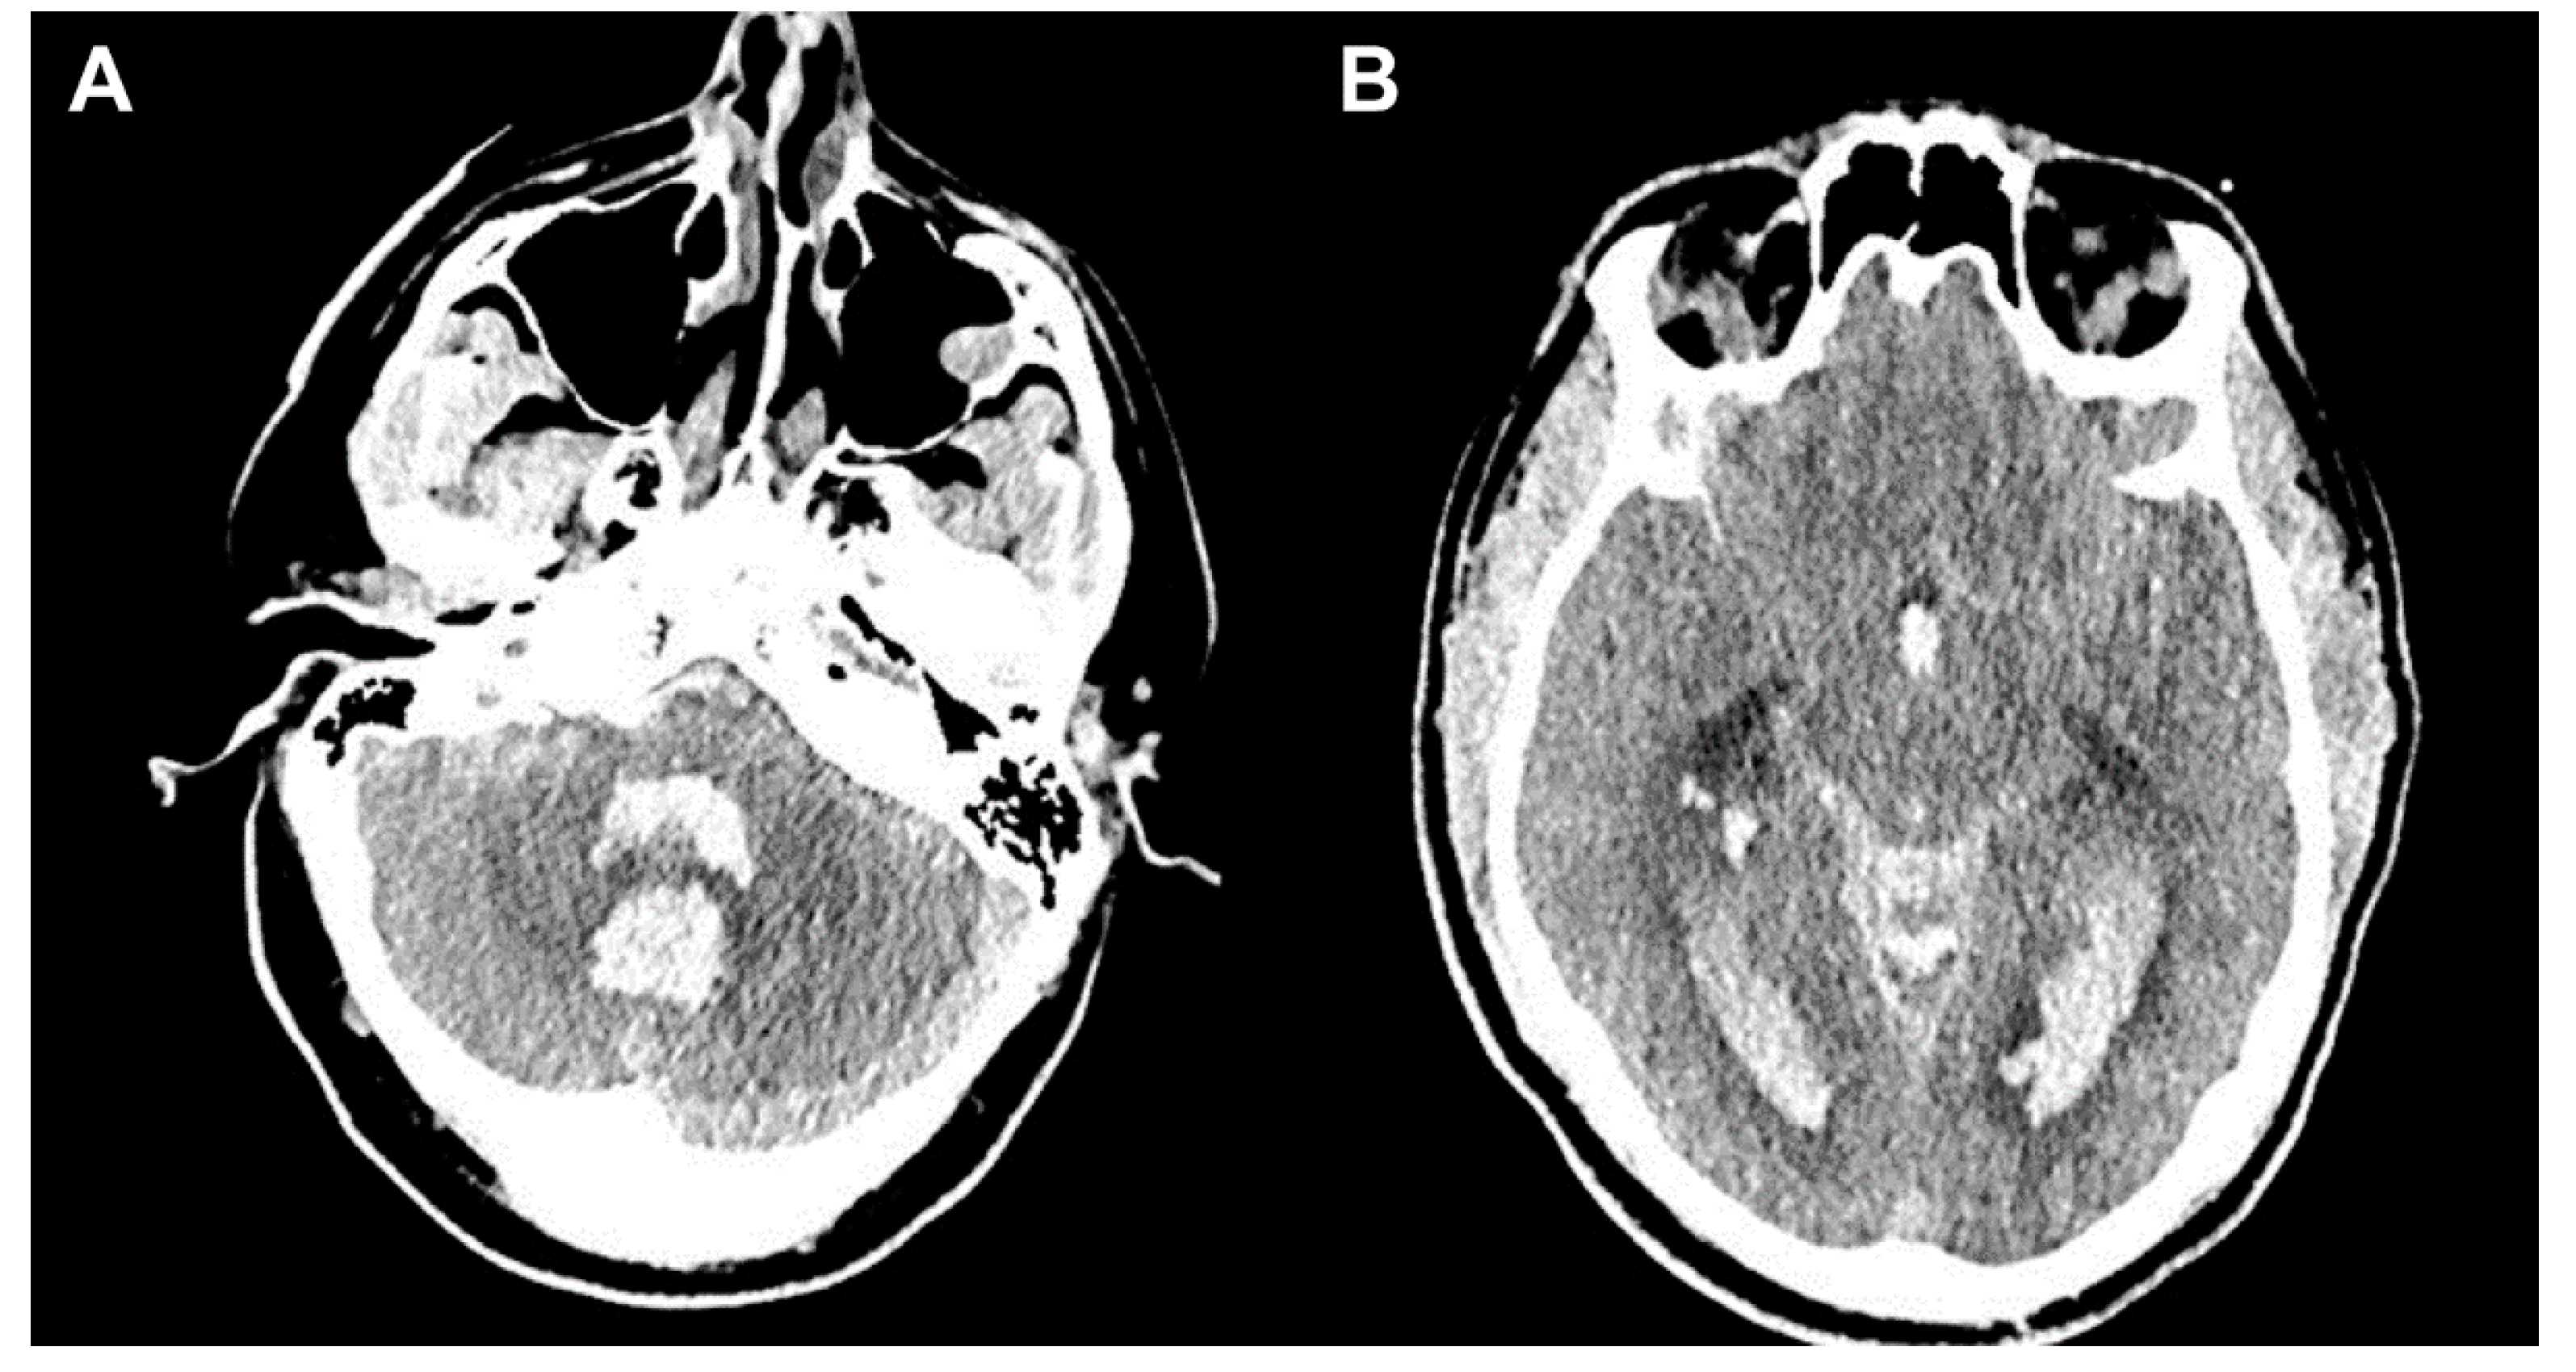

3.1. Case 1

3.2. Case 2

3.3. Case 3